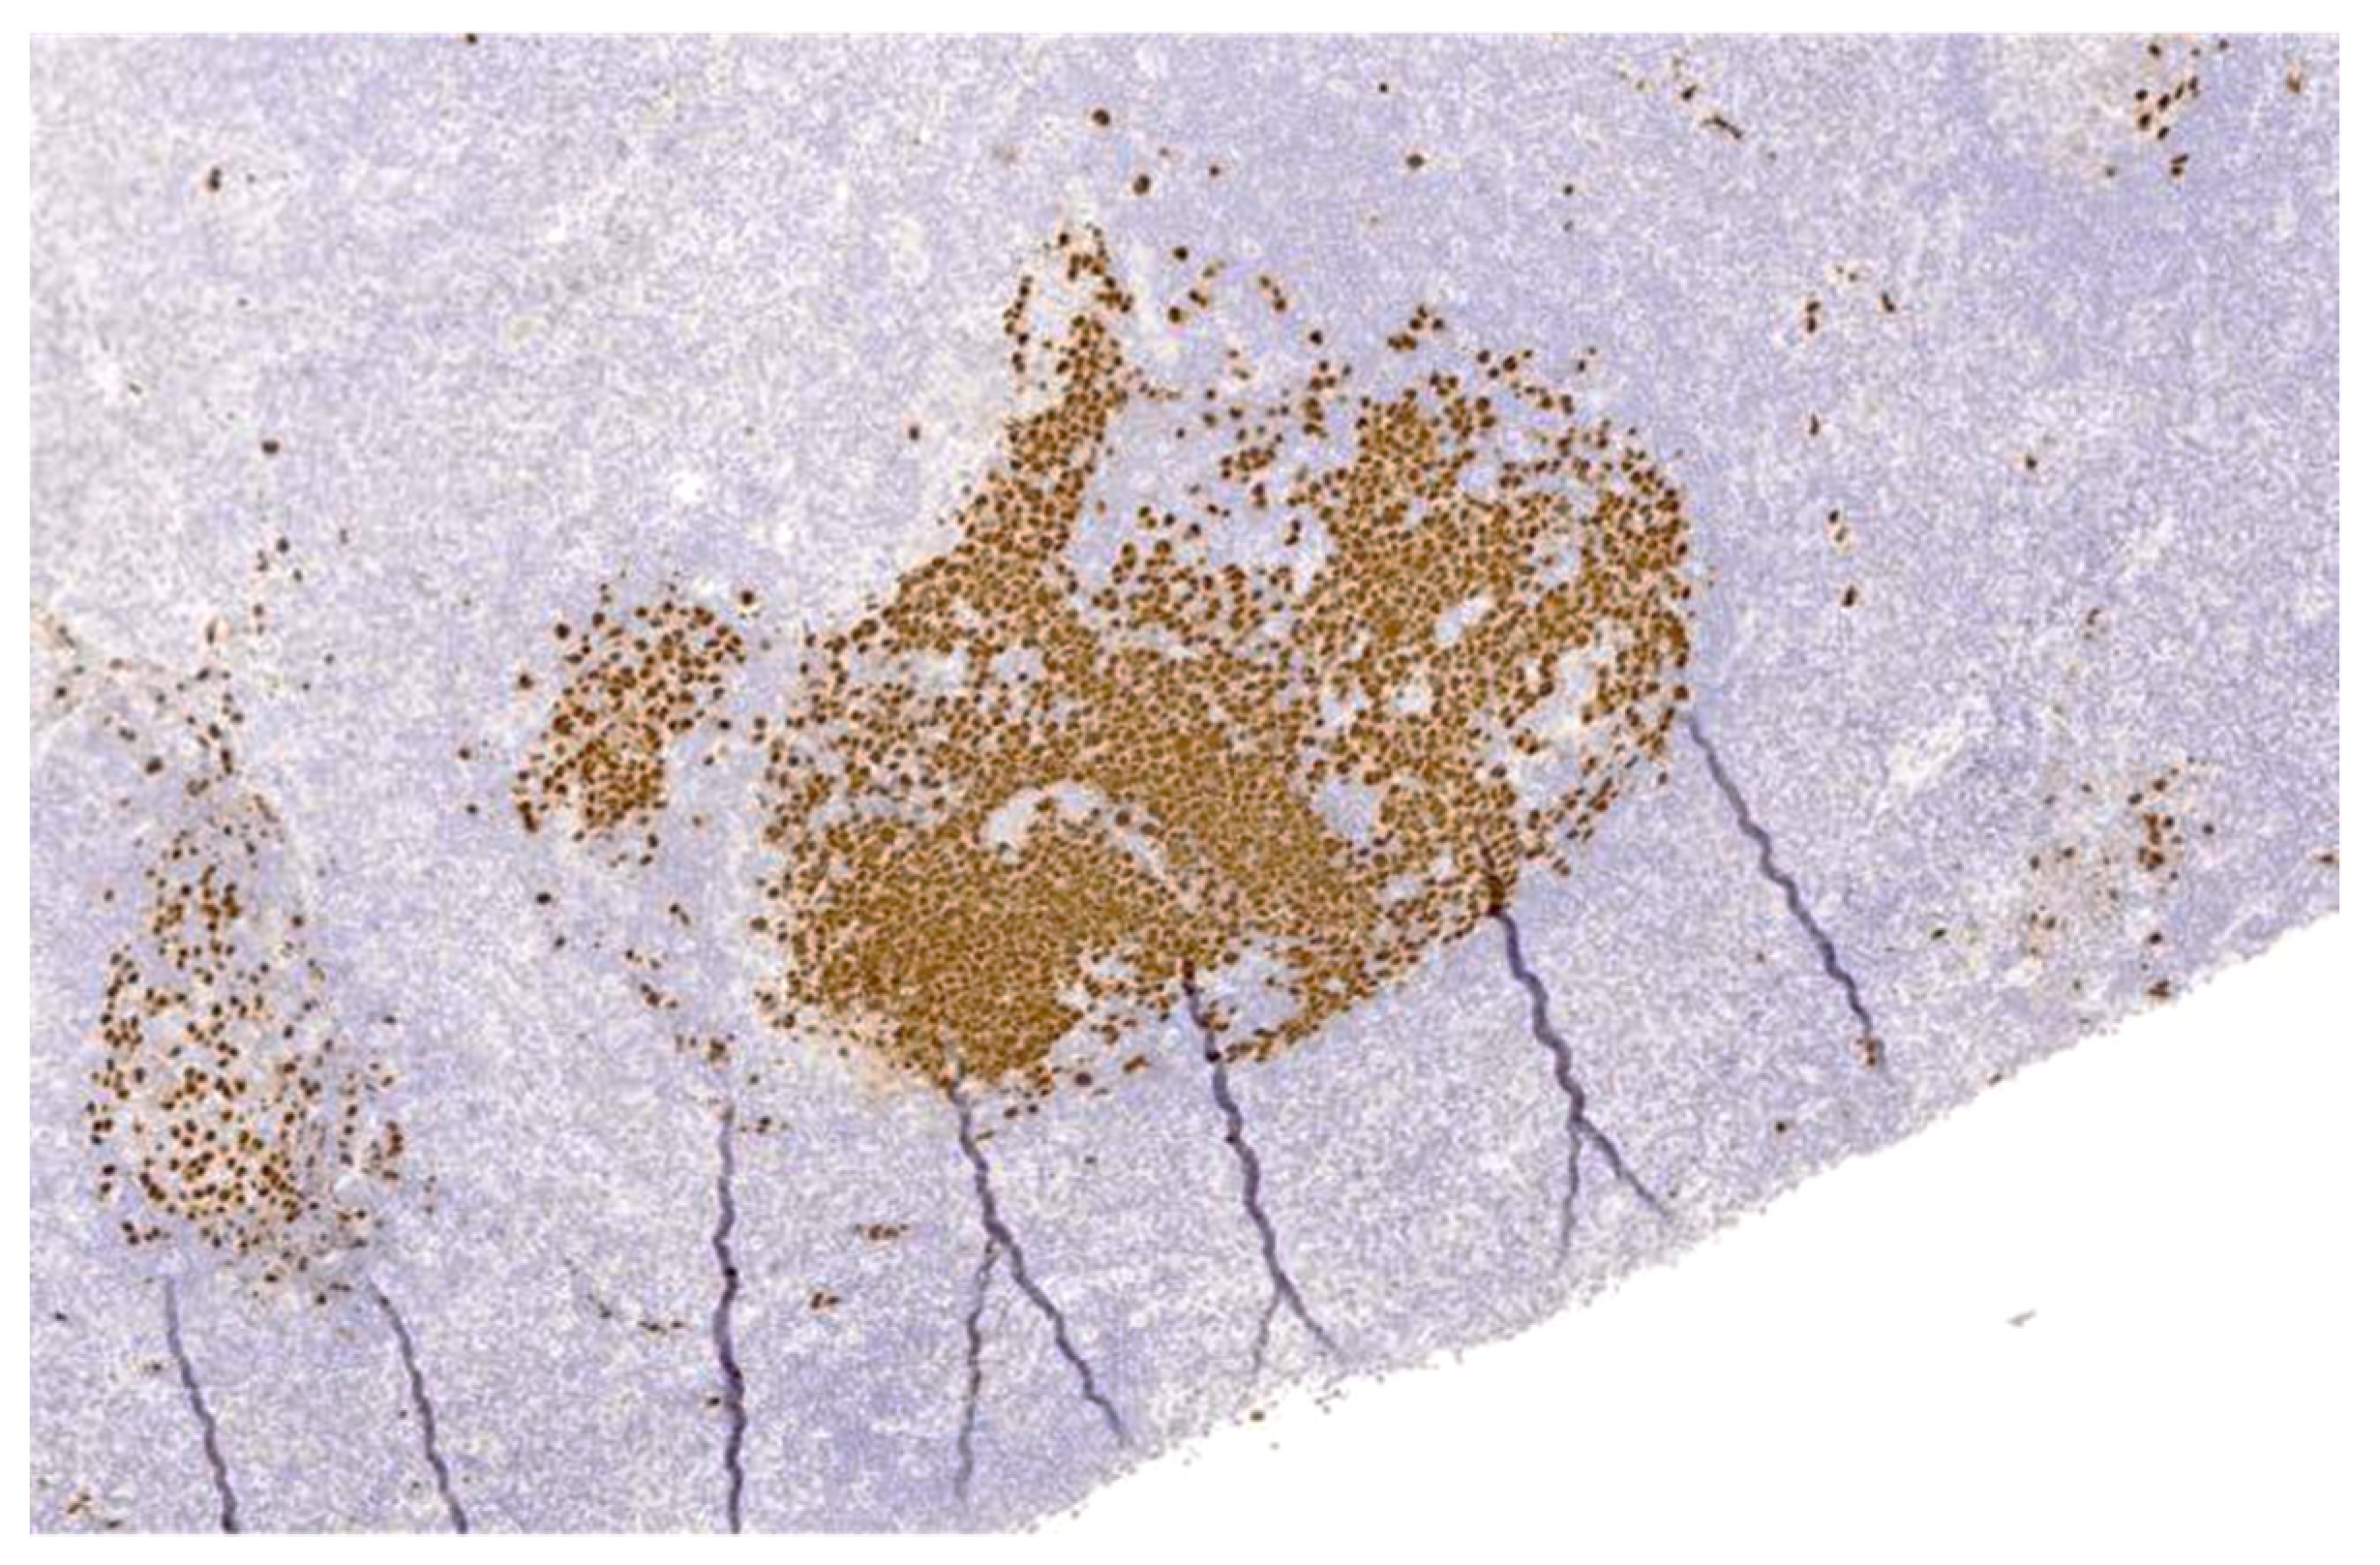

Figure 4. Germinotropic lymphoproliferative disorder. Immunohistochemical stain for KSHV/HHV8-encoded LANA shows co-infection of KSHV/HHV8 in the plasmablasts, within the involved germinal centres.

GLPD usually presents with localized lymphadenopathy, often without immunodeficiency. A plasmablastic proliferation is confined to expanded germinal centres, which are positive for cytoplasmic monotypic light chain, CD38, MUM1, KSHV/HHV8 viral IL6, LANA1, and EBV/EBER (Figure 3 and Figure 4).